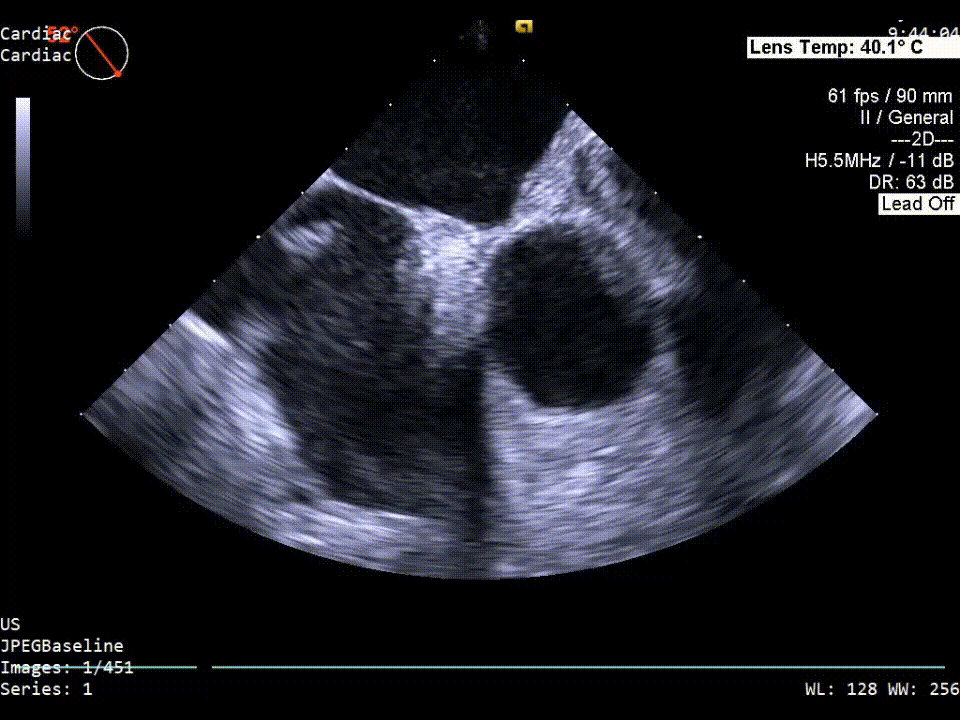

器械进入前超声再次验证PFO结构。

器械进入前cTEE发泡实验

器械进入前TEE彩超影像

建立通路超声影像

此例患者继发隔有些迂曲,继发隔缝合器到达卵圆孔附近后打开开合臂,开合臂张开后深入继发隔一段距离,收紧部分夹臂,再深入夹臂,完成最终继发隔捕获扣合。

继发隔缝合超声影像

xPlane影像下观察继发隔缝合器捕获情况,待确定为最佳位置后操作手柄对继发隔组织进行穿刺缝合。